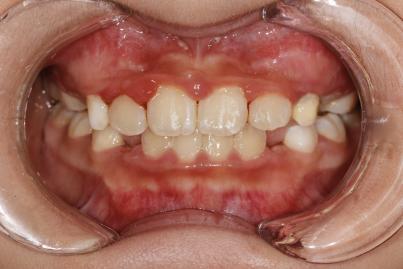

案例一:

治疗前

治疗后